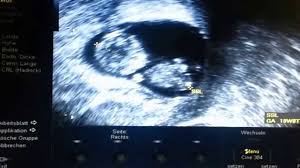

Das ist zu sehen. Lippen und Nase sind klar erkennbar. Der Embryo ist 25 cm groß.

SSW hat der Fötus eine Größe von etwa 3 cm und ein Gewicht von 4 g. Schwangerschaftswoche ist Ihr Baby rund drei Zentimeter groß also vergleichbar mit einer kleinen Erdbeere. SSW wird der kleine Embryo zum Fötus weil die Entwicklung der Organe und Körperteile nun abgeschlossen ist.

SSW noch nicht sehr ausgeprägt. Schwangerschaftswoche etwa vier Gramm und ist in der Scheitel-Steiss-Höhe zweieinhalb bis dreieinhalb Zentimeter lang.